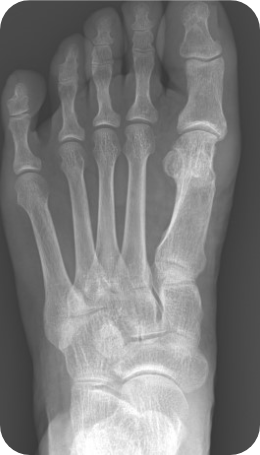

변형된 뼈 절골술을 시행한 후, 수술기구를 이용하여 고정합니다. X-ray 사진에 보이지 않는 흡습성 고정기구를 사용하기도 합니다.

▲ 무지외반증 교정술 후